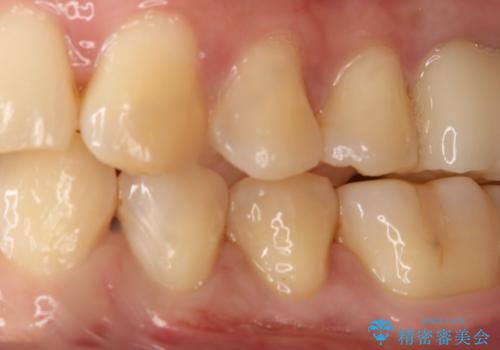

- 左下4番のう蝕を指摘され治療を希望された患者様です。

切削量などを考慮しクラウンでの治療を提案したところ、セラミックを希望されたのでフルジルコニアクラウンでの治療を選択しました。

う蝕が深かったので痛みが出る可能性をお伝えしましたが特に症状は現れなかったので、予定通りセラミッククラウンでの治療を行いました。